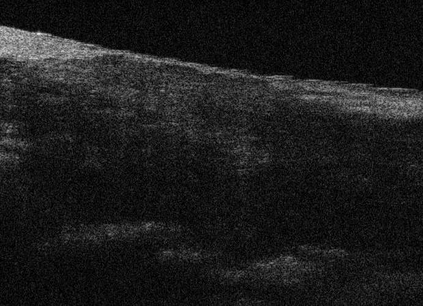

Coronary artery disease (CAD) is a cardiovascular condition with high morbidity and mortality. Intravascular optical coherence tomography (IVOCT) has been considered as an optimal imagining system for the diagnosis and treatment of CAD. Constrained by Nyquist theorem, dense sampling in IVOCT attains high resolving power to delineate cellular structures/ features. There is a trade-off between high spatial resolution and fast scanning rate for coronary imaging. In this paper, we propose a viable spectral-spatial acquisition method that down-scales the sampling process in both spectral and spatial domain while maintaining high quality in image reconstruction. The down-scaling schedule boosts data acquisition speed without any hardware modifications. Additionally, we propose a unified multi-scale reconstruction framework, namely Multiscale- Spectral-Spatial-Magnification Network (MSSMN), to resolve highly down-scaled (compressed) OCT images with flexible magnification factors. We incorporate the proposed methods into Spectral Domain OCT (SD-OCT) imaging of human coronary samples with clinical features such as stent and calcified lesions. Our experimental results demonstrate that spectral-spatial downscaled data can be better reconstructed than data that is downscaled solely in either spectral or spatial domain. Moreover, we observe better reconstruction performance using MSSMN than using existing reconstruction methods. Our acquisition method and multi-scale reconstruction framework, in combination, may allow faster SD-OCT inspection with high resolution during coronary intervention.